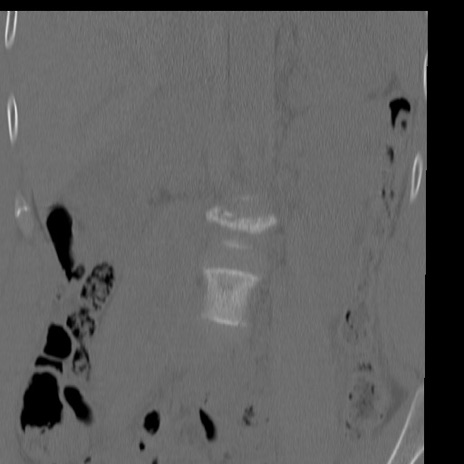

症例3 腰椎CT(冠状断像)

腰椎CT